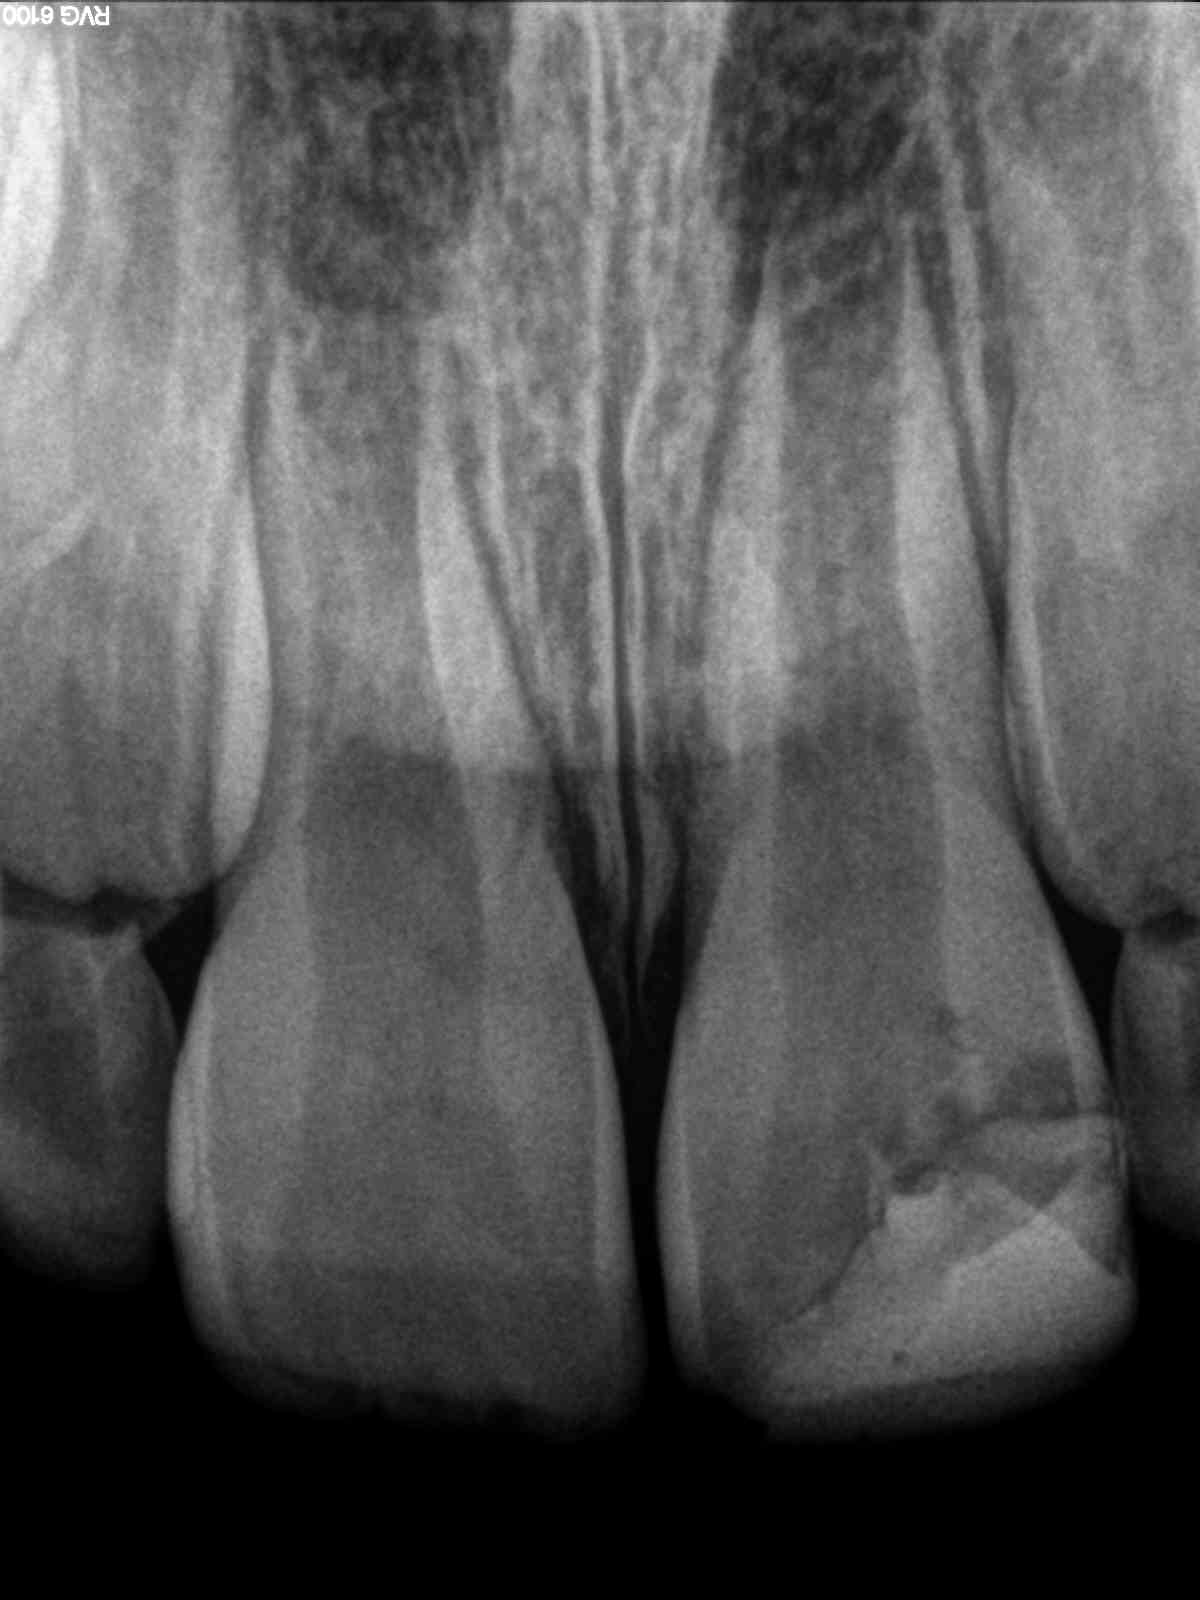

Chance Pulpotomie